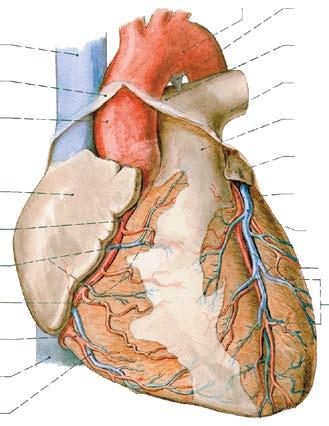

Srdce je uloženo v mediastinu, za sternem, svou jednou třetinou je vpravo od střední čáry, dvěma třetinami vlevo od střední čáry. Otisk srdce, prostřednictvím obalu srdce – perikardu – je patrný na obou plicích. Prostřednictvím perikardu nasedá srdce na bránici (obr. 5).

Obr. 5. SRDCE V PERIKARDU, uložené v mediastinu; perikard označen zeleně, jeho přední stěna byla odstraněna; odstraněny jsou i přední stěny obou pleurálních dutin

1 vazivová vrstva perikardu

2 srdce – facies sternocostalis

3 bránice – centrum tendineum

4 parietální pleura – pars diaphragmatica

5 okraj řezu parietální pleurou v její pars costalis

6 háček vyklápějící pravou plíci

7 pars mediastinalis parietální pleury

8 nervus phrenicus dexter

9 vena cava superior

Na povrchu srdce se rozeznávají plochy: facies sternocostalis (anterior) – přední vyklenutá plocha, obrácená proti přední stěně hrudníku (obr. 8); tuto přední stěnu tvoří hlavně přední stěna pravé komory, odkud vystupuje kmen plicnice, vlevo je zde úzký pruh levé komory, odkud za plicnicí začíná aorta, při bazi srdeční se na přední ploše nachází část

10 vena brachiocephalica sinistra

11 aorta ascendens (úsek aorty uvnitř perikardu)

12 arcus aortae

13 truncus pulmonalis, část uvnitř perikardu (tato tepna vede krev zbavenou kyslíku, proto se označuje modře)

14 nervus phrenicus sinister

15 nervus vagus sinister přiloženy k arcus aortae

16 háček vyklápějící levou plíci

pravé předsíně – ouško – auricula dextra (viz dále) a vlevo hrot ouška levé předsíně (auricula sinistra); facies diaphragmatica (inferior) – spodní, k bránici připojená plochá stěna, tvořená zadními stěnami pravé i levé komory (klinicky bývá označována jako „zadní stěna“);